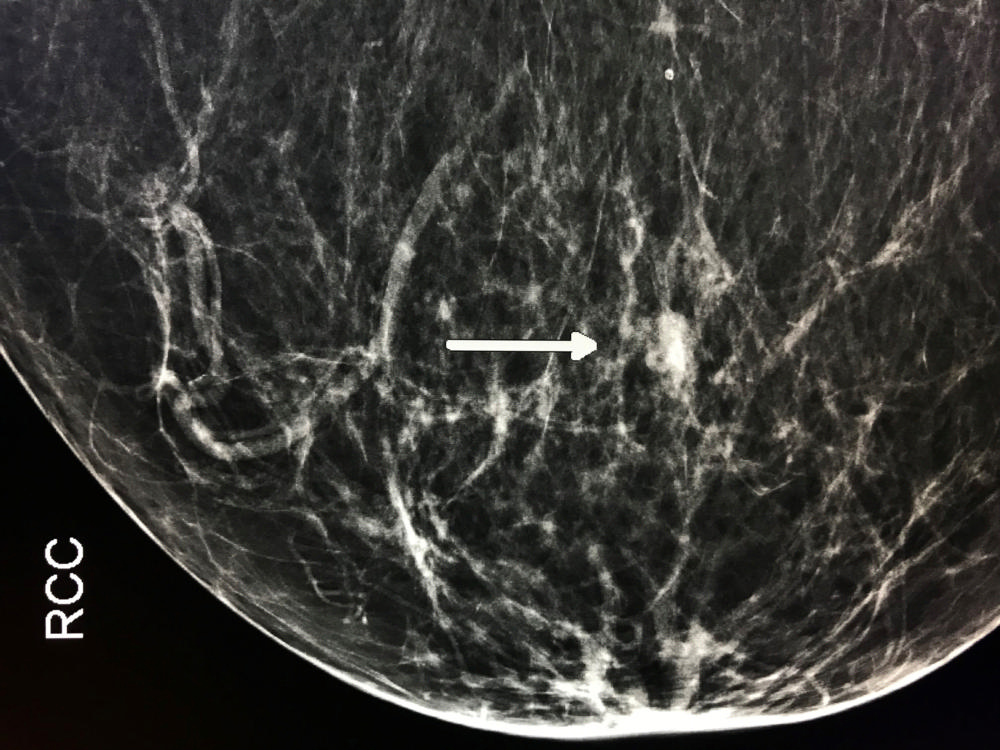

Figure 6. Mammogram demonstrates cancer in right breast prior to cryoablation (arrow).

High-res (TIF) version